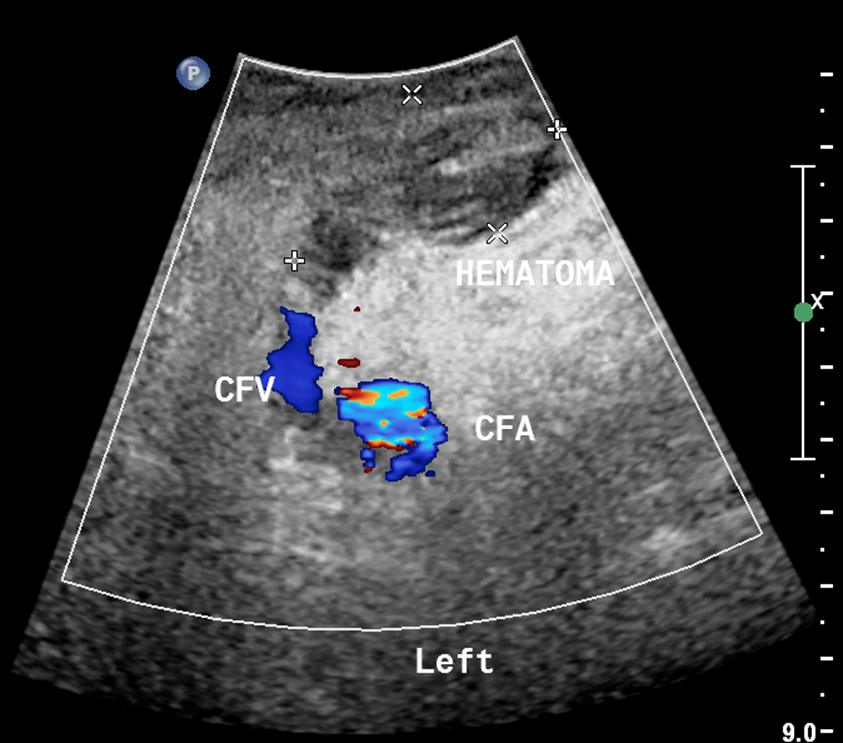

What is this image showing?

a hematoma